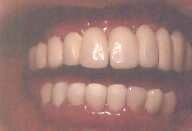

La kazo de alia sinjorino: Ŝi perdis la dentojn pro gingivaj malsanoj - ŝi ne scias bone zorgi pri siaj dentoj kaj gingivoj - kaj finfine ili estis preskaŭ falantaj. Oni devis forpreni ili, kaj anstataŭi ilin per metalaj radikoj (kompreneble, titanaj radikoj), post 6 monatoj oni malfermis ilin, oni faris provizorajn dentojn ĝis la ripariĝo de la gingivo, kaj fine oni konstruis porcelanajn dentojn.

De la perdo de la naturaj dentoj ĝis la fino de la kuracado, ŝi uzis , kompreneble, tutan depreneblan superan protezon, kaj ŝi ne estis feliĉa, ĉar ŝi ne povis bone maĉi. Kaj tio okazas al ĉiuj homoj, kiuj uzas artefaritan dentaron. Ekzemple: Ili ne povas mordi malmolajn manĝaĵojn ĉe la antaŭaj dentoj, ĉar tie estas la plej tikla loko de la superaj (kaj ankaŭ de la malsuperaj) dentaroj. Ili simple foriras de la gingiva bazo, kie ili kuŝas, se la homoj manĝas ekzemple pomon. Kaj post la kuracado ŝi estis tre feliĉa, ĉar ŝi denove povis mordi pomon.

![]() Bildo 6 a, b, c Fido kaj mem-apreco, denove. © D-ro R. Resende |

Dum 25 jaroj ŝi restis sen la antaŭaj dentoj, kaj pro tio la superaj postaj dentoj malsupreniris. Do mi devis fari kirurgion por suprenirigi la dentojn. Post la ostointegriĝo de siaj implantoj, oni malfermis la gingivon, faris provizorajn plantajn dentojn, kaj fine ŝi ricevis porcelanajn kronojn. Kaj nun ŝi povas perfekte ne nur manĝi sed amkaŭ ridi, prelegi, kaj eĉ preĝi sen la timo, ke la dentoj povu fali.